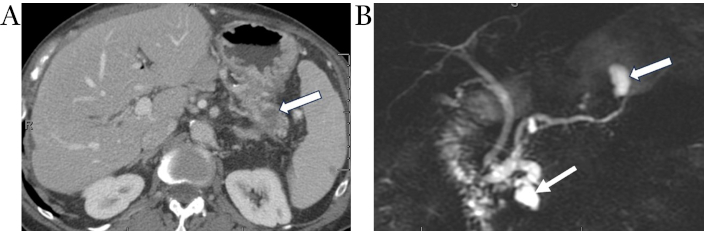

CT shows IPMNs as single or multiple cystic hypodense lesions. MD-IPMNs directly involve the MPD associated mucin hypersecretion resulting in ductal dilation over 5 mm often with progressive atrophy of overlying pancreatic parenchyma (Figure 4A and 4B). BD-IPMNs may be unilocular, multicystic, or may have a tubular morphology (Figure 5A). Mixed-type IPMNs have features of both the BD-IPMNs and MD-IPMNs (Figure 5B) [18]. On MRI, IPMNs are hyperintense on T2-weighted imaging and demonstrate low signal on T1-weighted imaging due to its mucinous content. Communication with pancreatic duct is commonly noticeable. Enhancing mural nodules and pancreatic ductal dilation are better identified on MRI when compared to CT imaging [54].

Main duct IPMN. Axial contrast-enhanced CT image (A) demonstrates diffuse marked dilation of the main pancreatic duct (white arrows). Coronal contrast-enhanced CT image (B) obtained 1-year later shows scattered enhancing mural nodules, a worry-some feature (white arrows). IPMN: intraductal papillary mucinous neoplasm

Metachronous pancreatic adenocarcinoma consistent with field-defect. Coronal MRCP image (A) demonstrates mixed IPMN with segmental dilation of main duct in the pancreatic head (arrowhead) and cystically dilated branch ducts in pancreatic head and tail. Axial contrast-enhanced CT image (B) obtained 3 years after Whipple procedure for adenocarcinoma of pancreatic head shows new focus of hypo-enhancing mass in the tail (white arrow) away from the previously documented main duct and branch duct IPMNs (arrowhead), consistent with the “field defect” phenomenon in the remnant pancreas. IPMN: intraductal papillary mucinous neoplasm

MD-IPMNs and mixed-typed IPMN demonstrate malignant transformation in approximately 45% of resected samples [6, 8]. In comparison with BD-IPMN, which exhibits a rate of advanced neoplasia in around 10–20% of resected specimens [6, 8]. Guidelines aimed at identifying worrisome and high-risk features for BD-IPMN have been set fourth, including the Sendai criteria followed by the Fukuoka guidelines which have been revised in 2017 and most recently the Kyoto guidelines [9, 55]. A recent study hypothesized that dilation of the uncinate duct is a radiographic indicator of high-risk disease, specifically IPMN associated with HGD or IC [56, 57]. IC may develop at a site distant from the primary location of the IPMN at a later stage, supporting the concept of field defect and dual carcinogenesis. This emphasizes the importance of radiological evaluation of the entire pancreas and further surveillance of the residual pancreas following resection of the cystic lesion [58].